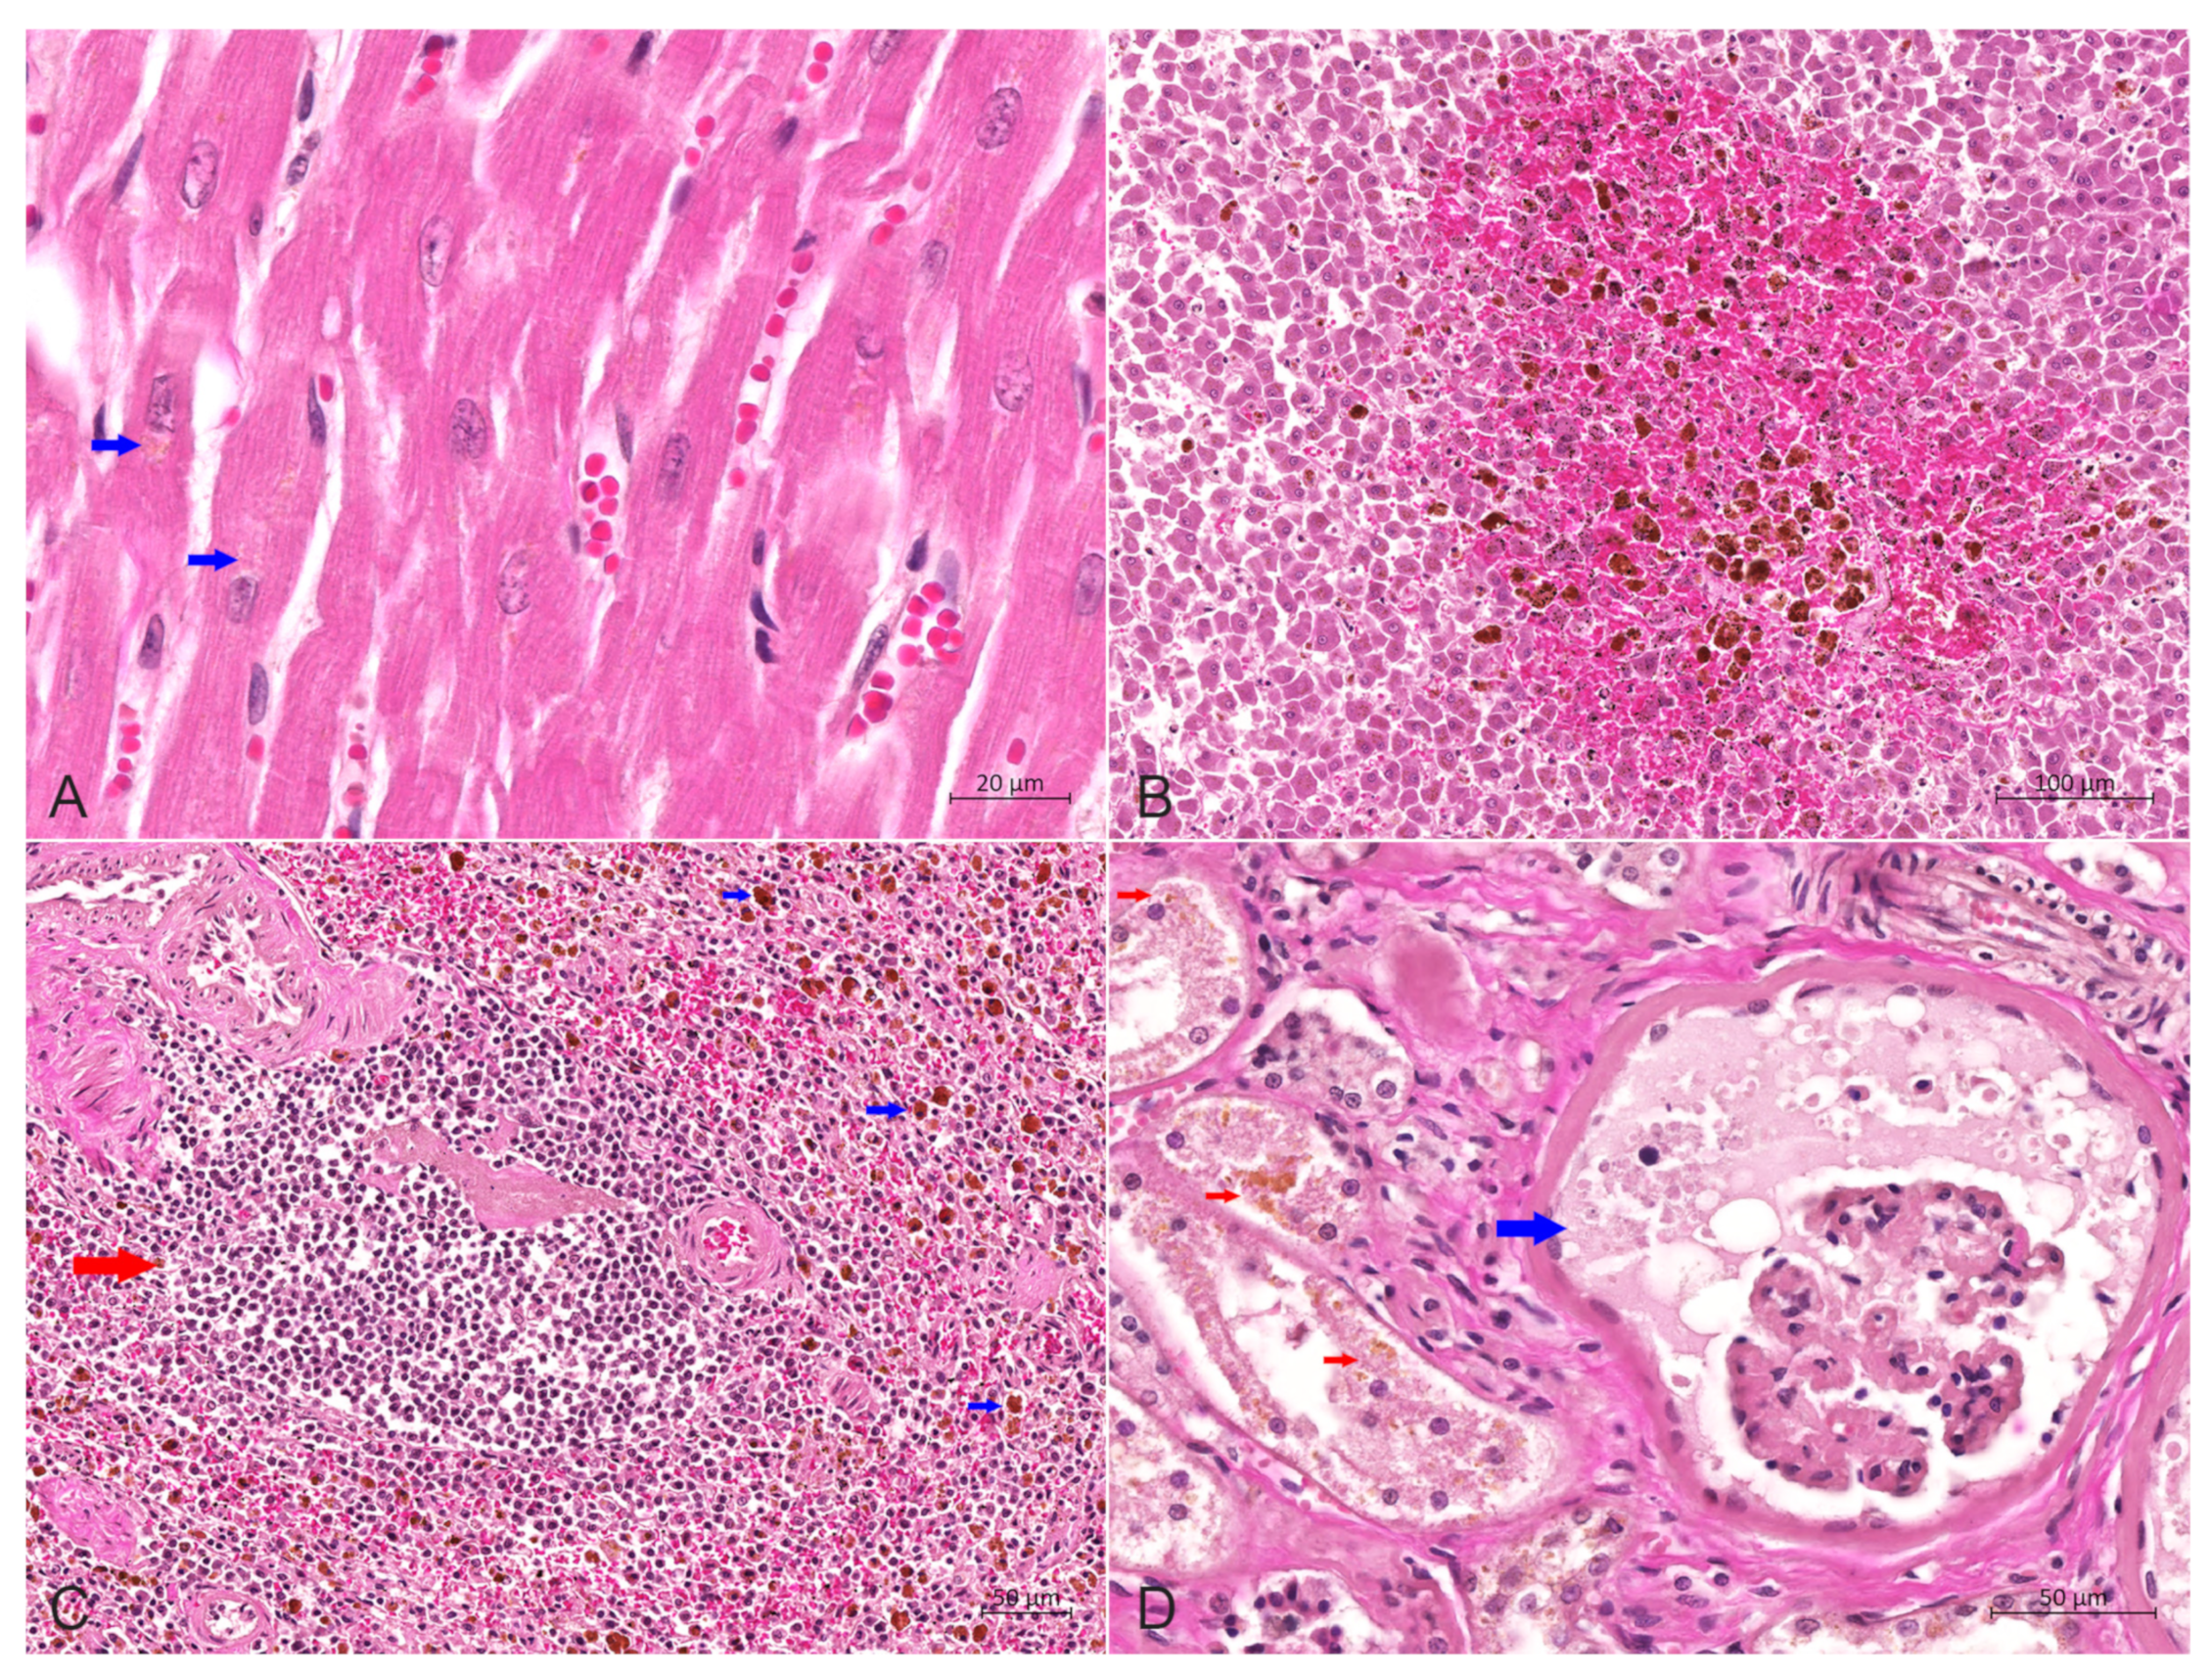

2.3. Histopathology

The main histopathological features of the lung included scattered or dense proliferative histiocytic cells (PHCs) in the bronchioles at all levels and in the alveolar cavities, as well as connective tissue hyperplasia in the interstitium (Figure 4A,B). The lobular, bronchiolar and alveolar structures of the lung disappeared and were filled with many PHCs (Figure 4A). The pulmonary septal spaces in the consolidation areas were markedly widened, caused by severe fibrosis in the interstitium (Figure 4B). PHCs had a large volume and were circular, elliptical or irregular in shape (Figure 4C). Most of such cells exhibited pseudopodial protrusions from their surfaces, connecting them. The cytoplasm was rich and pale pink, with some cells showing vacuolar lipid droplets in the cytoplasm. The nuclei were circular, elliptical or reniform, with clearly visible nucleoli, and a mitotic appearance of the nuclei was occasionally seen, as well as binucleated cells (Figure 4C,D). Type II alveolar epithelial cells showed mild or distinct proliferation, with partial detachment of bronchial epithelial cells at all levels, and scattered infiltration of neutrophils and lymphocytes was present in the alveolar cavity (Figure 4D). There was edema in the submucosa of bronchioles, where PHCs were scattered. Some areas of lung tissue displayed diffuse necrosis, forming interconnected necrotic foci with varying sizes and shapes.

Figure 4. Hematoxylin-eosin stain of the lung. (A) The lobular, bronchiolar and alveolar structures of the lung disappeared and were filled with a large number of PHCs, bar = 500 μm. (B) Proliferation of numerous histiocytic cells in the alveolar cavity (left) and bronchioles (right), with severe fibrosis in the interstitium, bar = 100 μm. (C) The alveolar cavity was repleted of PHCs, with occasional mitotic figures (blue arrow), and type II alveolar epithelial cells (red arrow) showed prominent hyperplasia, bar = 20 μm. (D) A large number of PHCs in the alveolar cavity with occasional binucleated cells (blue arrow), bar = 20 μm.